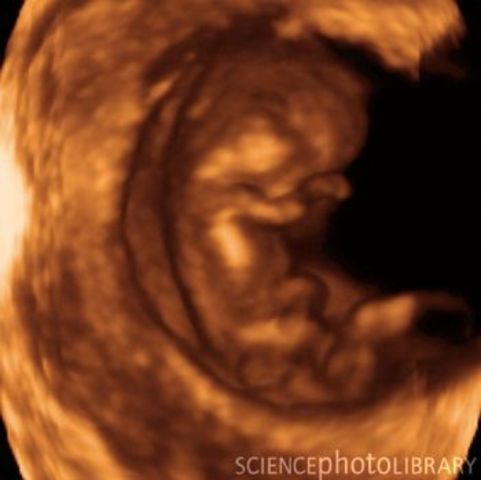

• 8 weeks

8 weeks

Webbed fingers and toes are poking out from your baby's hands and feet, his eyelids practically cover his eyes, breathing tubes extend from his throat to the branches of his developing lungs.